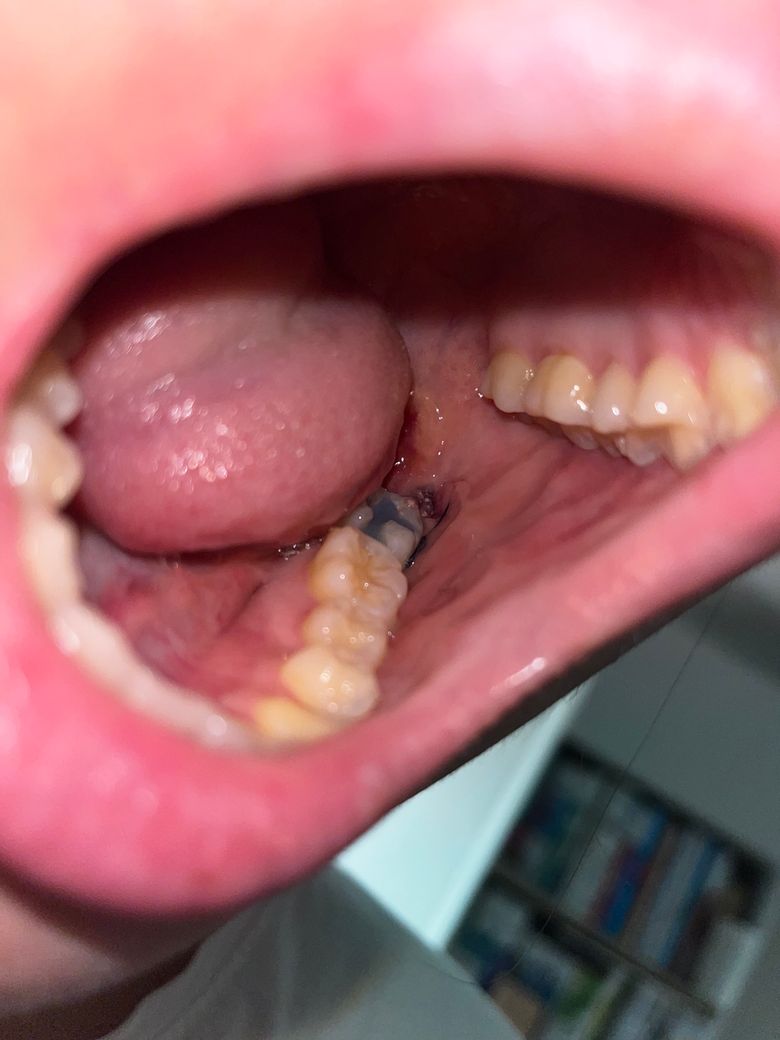

매복사랑니 발치 후 혈전안에 하얀색이 뭔가요?

매복사랑니를 이번주 목요일날 발치하여서 현재 3-4일차 입니다. 사랑니 발치한 자리 혈전에서 하얀색 덩어리들이 보이는데 이게 뭔지 궁금합니다. 처음에는 이물질인줄 알고 물가글을 해보았는데 안없어지는걸로 보니 이물질은 아닌것같은데.. 뭘까요?

그리고 발치한 부분 옆에도 빨갛게 부어올랐습니다ㅠㅠ

• 1번 째 사진